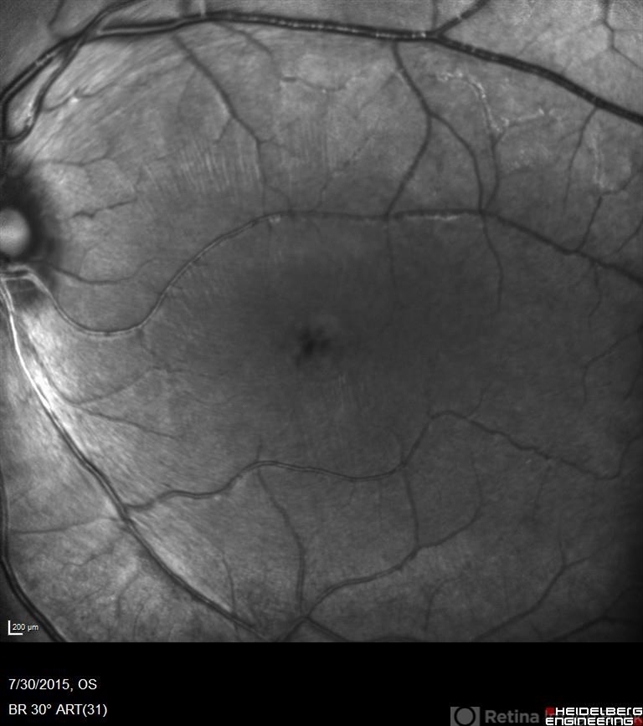

- retinal dystrophy, Goldmann-Favre Syndrome, juvenile retinoschisis

- Fluorescein angiography of a 24-year-old male. Juvenile retinoschisis on OCT. FA shows outer retinal staining. Could be associated with Goldman Farve Syndrome.